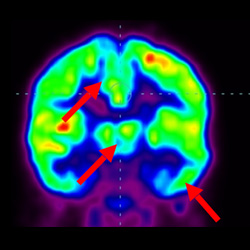

細胞治療前 PET CT 掃描顯示神經(jīng)組織中的藍/黑色區域,表明腦癱引起的大腦損傷。

細胞治療后,藍色和黑色區域減少,并且看到更活躍的區域。這表明損傷減少并改善了大腦功能。

這證明細胞療法是治療腦癱兒童安全有效的方法。細胞療法可以更新大腦損傷的核心,并且可以通過(guò) PET CT 掃描來(lái)監測大腦的改善情況。這些細胞療法與標準治療一起促進(jìn)腦癱兒童的生長(cháng)和改善。